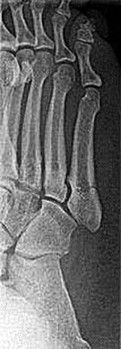

A 25-year-old male injures his midfoot when falling from a horse with his foot caught in the stirrup. Radiographs show a widening of the space between the base of the 1st and 2nd metatarsals. Which ligament is primarily ruptured in a classical Lisfranc injury?

Options:

- Ligament connecting the 1st metatarsal to the medial cuneiform

- Ligament connecting the 2nd metatarsal base to the medial cuneiform

- Ligament connecting the 2nd metatarsal base to the intermediate cuneiform

- Plantar fascia

- Spring ligament

Correct Answer: Ligament connecting the 2nd metatarsal base to the medial cuneiform

Explanation:

The Lisfranc ligament connects the medial cuneiform to the base of the second metatarsal. It is a critical stabilizing structure of the midfoot, and its rupture leads to instability.